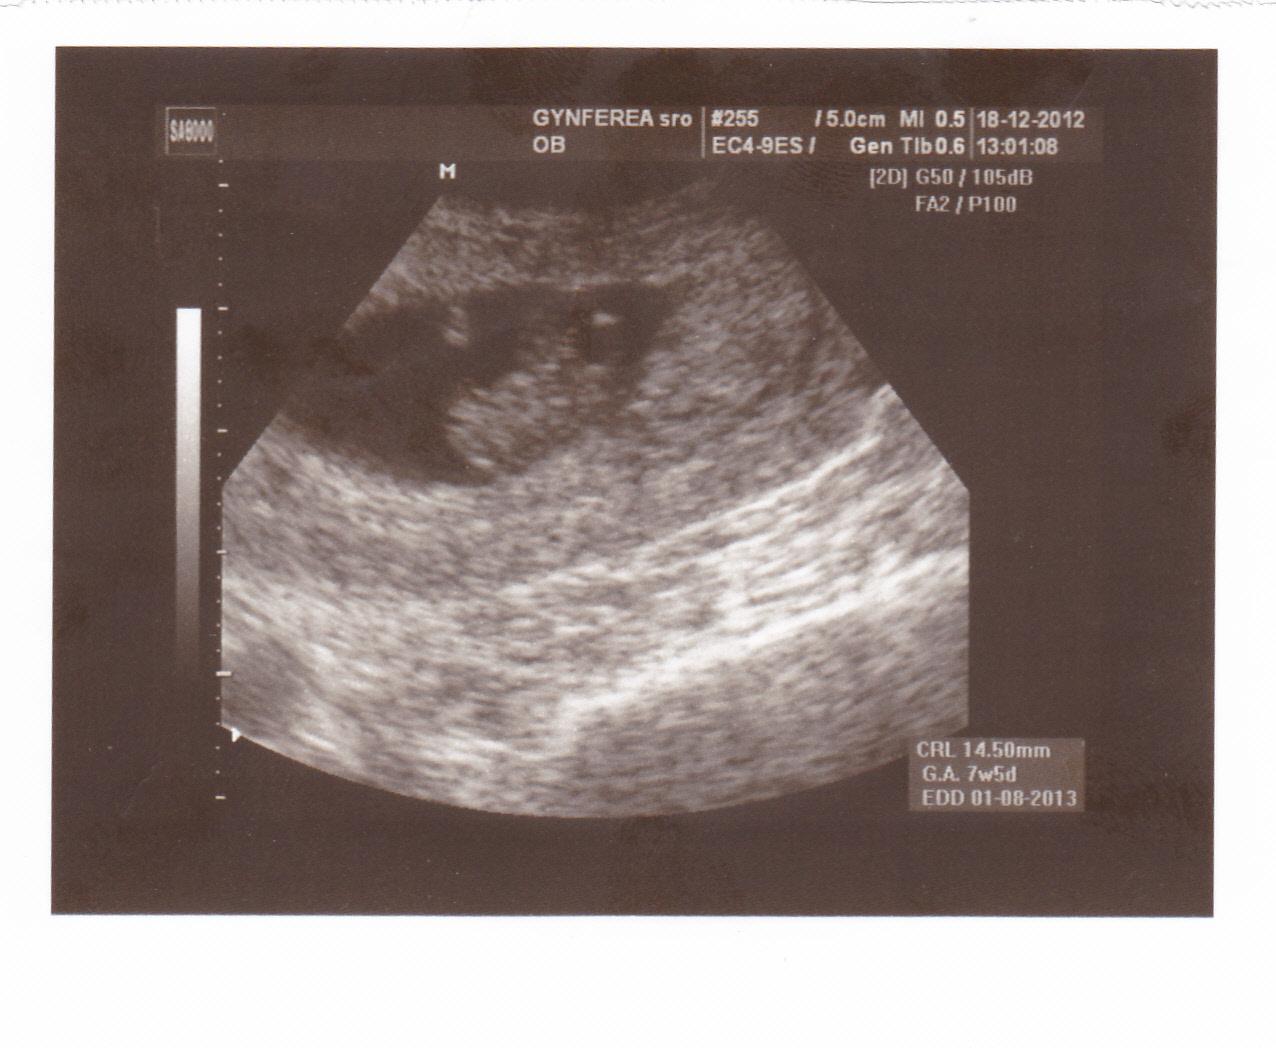

tak som bola u lekara, dal mi torecan ze ak uz bude moc zle a homeopatikum cocculine. Tak skusim najprv cocculine a ked bude moc zle, tak si dam aj cipok, ale je mi hnusne stale, urobil sono zas a malilinkate srdenko sa zacina objavovat a objednali ma na sono az na 12tt

nase mimi 😵 😵 7+5tt, 14,5 mm 😵 😵 dnesne sono